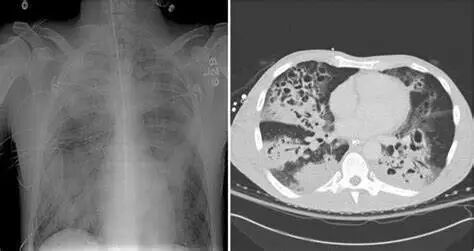

皮肤和软组织一直是CA-MRSA感染的主要部位,但CA-MRSA也可导致侵袭性严重疾病,例如坏死性肺炎、骨髓炎、泌尿道感染、感染性心内膜炎和脓毒症。

继发的重症金葡菌肺炎是流感致死的常见原因